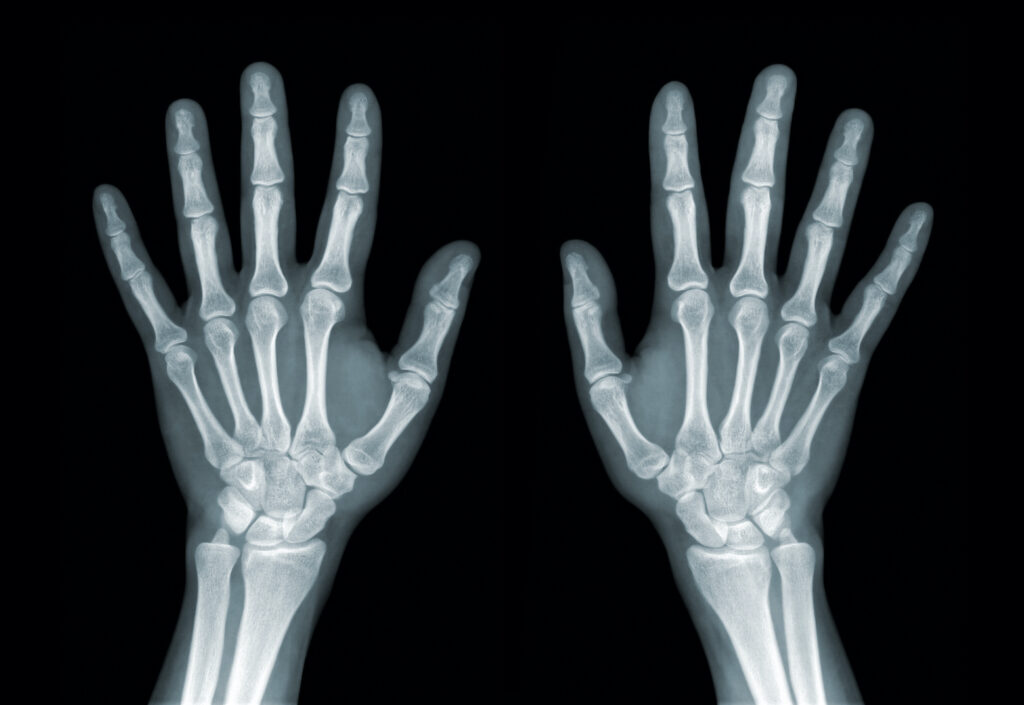

As a result of this, fluid accumulates around the joints causing pain, stiffness, tenderness and inflammation. RA is also a symmetrical disease in it affects both sides of the body simultaneously. It generally begins in the smaller joints such as the fingers and can eventually spread into the larger joints as well as the hips, shoulders and ankles. Because RA is an autoimmune disease it can affect the entire body, not just the joints.

OA does not involve the immune system like RA does, and doesn’t tend to affect both sides of the body at once. OA will generally target the large weight bearing joints, like the hip or knee on one side of the body. People with OA will not experience full body symptoms like RA, and symptoms are limited solely to the joints themselves.